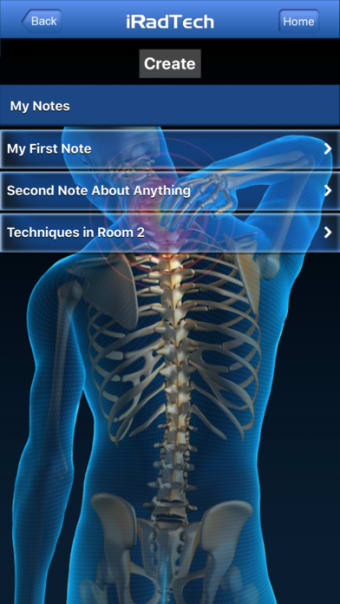

IRadTechهو برنامج إصدار كامل لأجهزة iPhone ، وهو جزء من فئة "الطب" أ>.

حول IRadTech لأجهزة iPhone